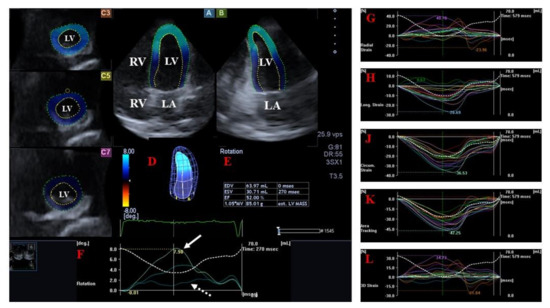

- Kormányos, Á.; Domsik, P.; Kalapos, A.; Orosz, A.; Lengyel, C.; Valkusz, Z.; Trencsányi, A.; Forster, T.; Nemes, A. Left ventricular twist is impaired in acromegaly: Insights from the three-dimensional speckle tracking echocardiographic MAGYAR-Path Study. J. Clin. Ultrasound 2018, 46, 122–128. [Google Scholar] [CrossRef]

- Nemes, A.; Kormányos, Á.; Domsik, P.; Kalapos, A.; Lengyel, C.; Valkusz, Z.; Forster, T. Left ventricular ‘rigid body rotation’ in a patient with acromegaly (from the MAGYAR-Path Study). Quant. Imaging Med. Surg. 2017, 7, 378–379. [Google Scholar] [CrossRef]